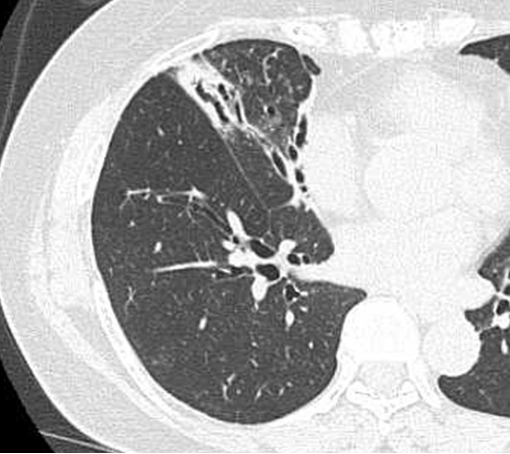

健康診断等での胸部単純エックス線画像で,気管支壁の肥厚や嚢胞状に拡張した気管支所見が認められ診断されることもありますが,軽度な症例では はっきりしないこともあります。最も有用な診断方法は胸部CTです。特に高分解能CT(HRCT)の普及により,無症状の気管支拡張症が発見されることが多くなっています。また感染が疑われる場合は病原菌を同定するために痰の培養検査を行います。喀血が多い時は,気管支鏡検査で気管内腔を確認したり,血管造影を行い異常血管を確認することがあります。

気道の拡張:2つ以上の気道の内腔が近接する動脈径より大きいことにより判断します。signet ring sign(体軸横断像で肥厚,拡張した気道がより口径の小さい動脈に接している像)と呼ばれます。

正常な気管支の先細りがないことにより,ほぼ胸膜まで中サイズの気管支が可視化されまず。軌道陰影(tram lines)と呼ばれます。